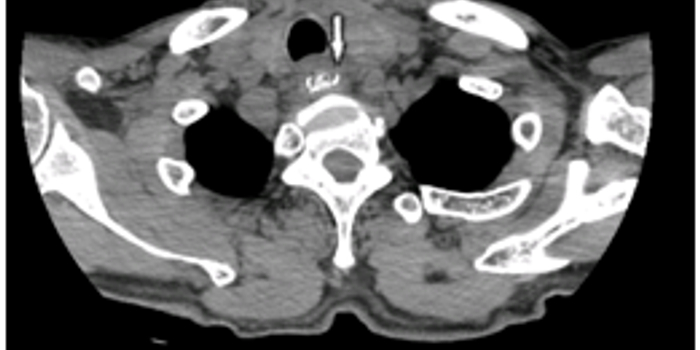

医院消化内科谢立群主任接诊后,对患者病情进行详细了解,检查结果显示,范大爷食管上段异物,食管右侧穿孔。考虑到枣核在食道内已经停留4天,目前已出现食管穿孔,如果治疗时间再有耽搁,可能会导致纵膈、胸腔感染以及血管破裂导致大出血,危机生命。

经过紧张的准备,手术顺利实施。手术过程中发现在食管距门齿17厘米处,也是食管上段最狭窄的地方,一颗大枣核嵌顿,枣核两端已深深扎入食管壁内。